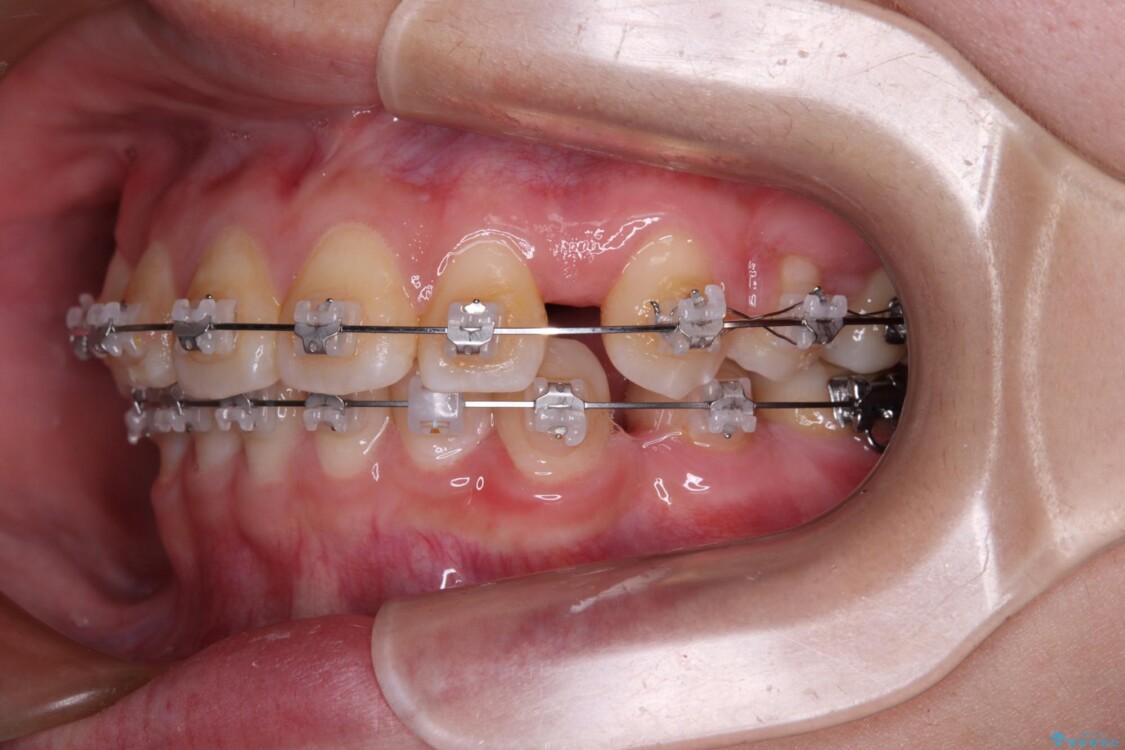

治療途中

• 転勤でも安心して治療継続 抜歯スペース閉鎖と深い噛み合わせ改善のワイヤー矯正 治療途中画像